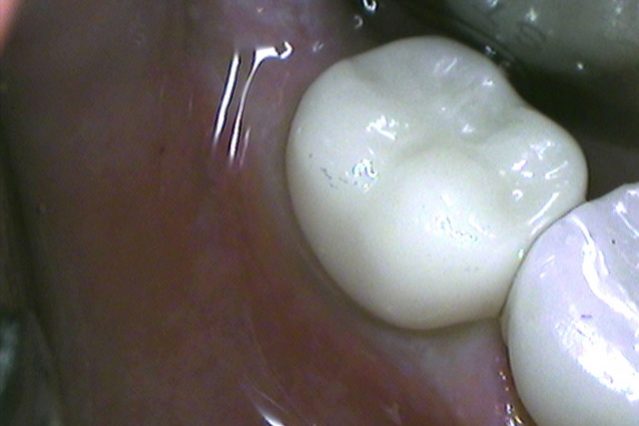

Successful implant treatment depends on the ability to act like natural teeth and be in harmony with the tissue and the bone. Basic precautions can be important for that and advanced level techniques must be performed by the clinician, and the implant must include the technology to imitate natural structure.